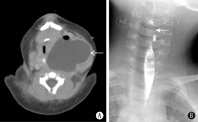

所有患儿均行颈部超声检查,多可见甲状腺旁不规则囊性包块。1例产前行MRI检查;36例生后行CT/MRI检查,其中31例(31/36,86.1%)包块内发现气体影(图1A)。33例(33/37,89.2%)气管受压移位;包块最大径(4.2±1.1)cm(2.5~6.9 cm)。甲状腺受累22例(22/37,59.5%),21例为推挤受累,1例合并甲状腺炎。12例(12/37,32.4%)行食管造影,仅1例(1/12,8.3%)见瘘管(图1B)。2例术前直接喉镜检查未见梨状窝开口。

食管造影和CT/MRI是诊断PSF最常用的影像学方法。食管造影被认为是诊断成人和儿童PSF的金标准[2],诊断率达74.6%~97.4%[11,12,13]。但本组病例中12例行食管造影,仅1例(8.3%)见到与梨状窝相通的细小瘘管从而诊断为梨状窝瘘,其余均未发现异常,提示食管造影在诊断新生儿PSF时阳性率低,还有误吸风险。原因可能与局部炎症、水肿、患儿无法配合有关;而CT/MRI检查的诊断率达86.1%,与其他文献报道相似[14]。CT/MRI检查在新生儿中诊断率高,还能同时显示肿物与周围组织的关系,以及气管、颈动脉鞘、甲状腺情况,建议疑诊新生儿PSF患儿优先选择CT/MRI检查。